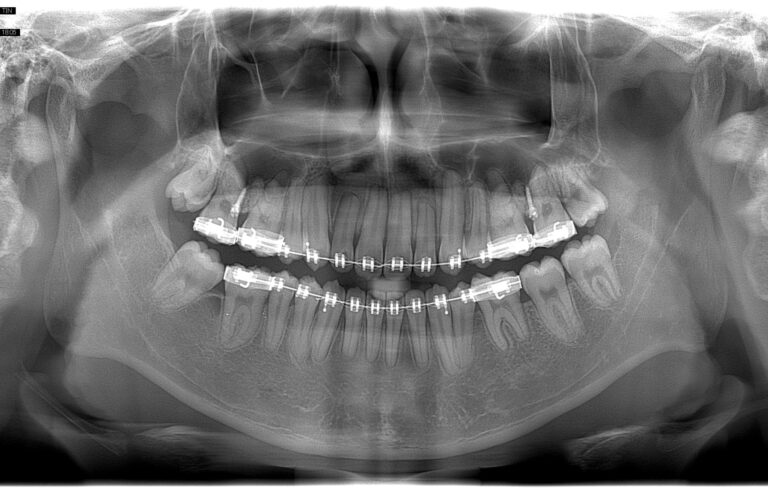

Các phim X-quang trong miệng

Các cuộc kiểm tra hình ảnh X-quang trong miệng là yếu tố chủ chốt trong việc chụp hình ảnh cho…